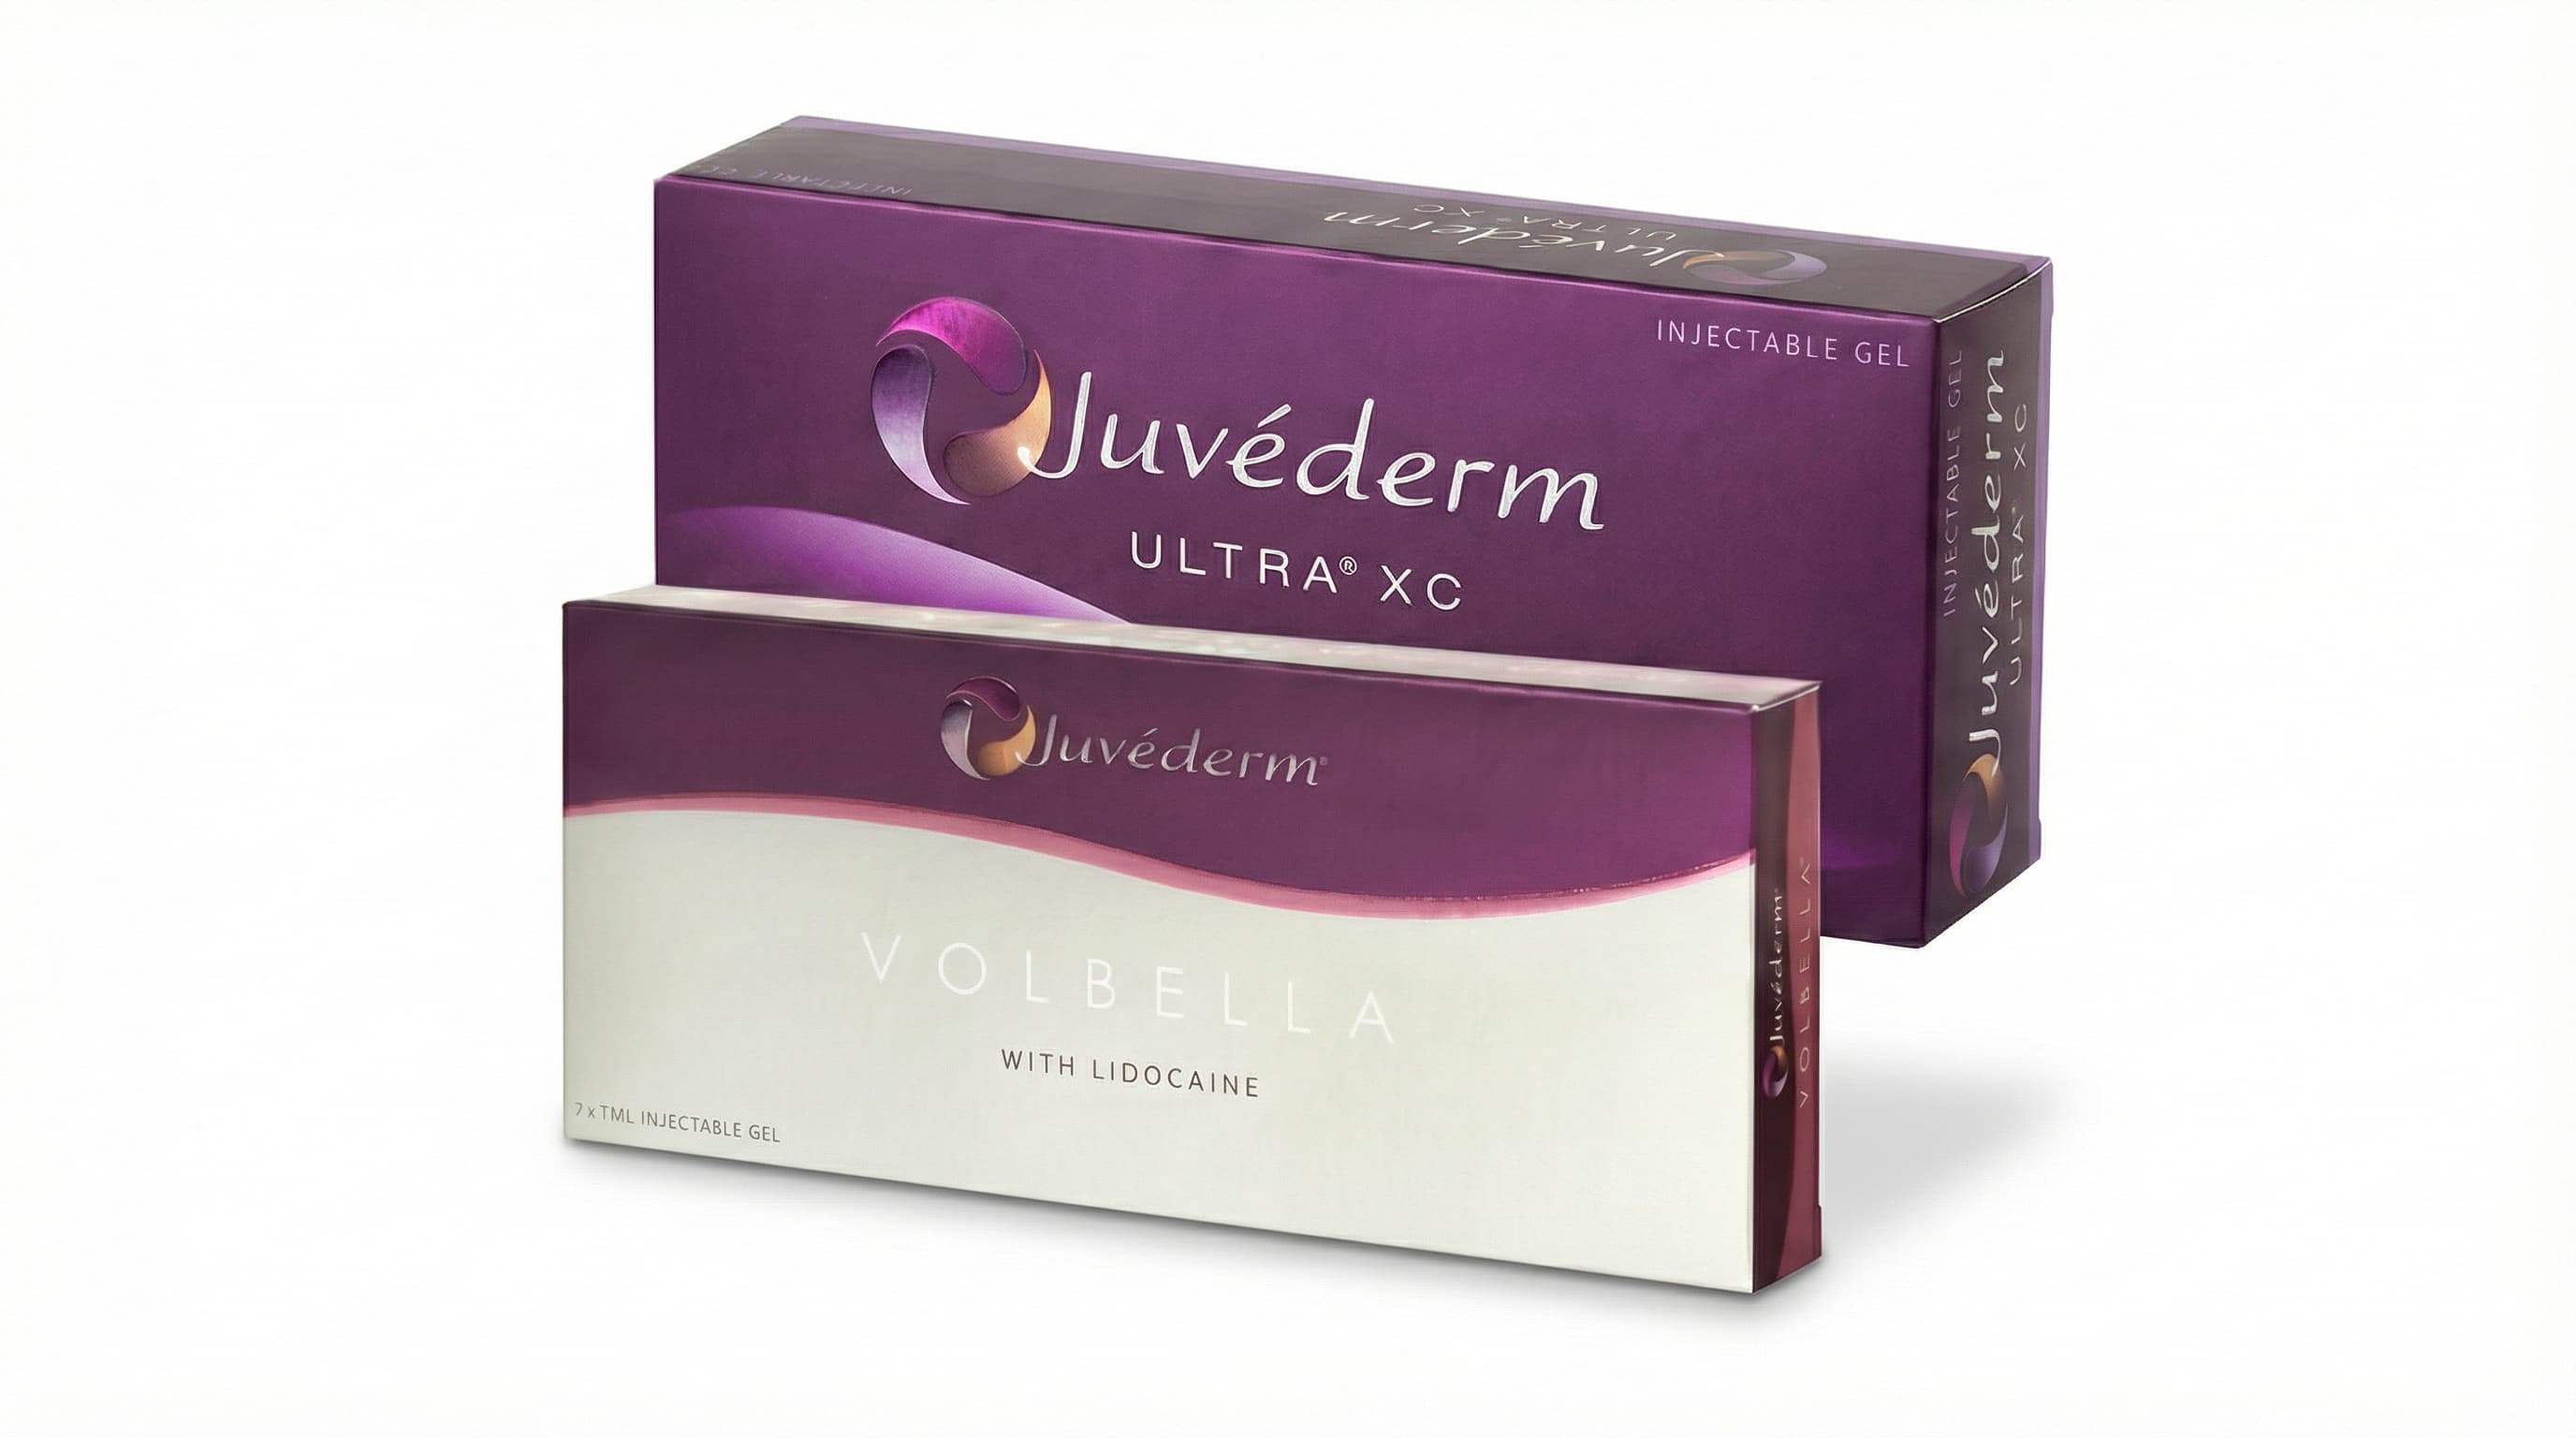

Hyaluronic Acid Injection (Y-Zone) Procedure injecting cross-linked hyaluronic acid into vaginal mucosa or vulva for volume and moisture. Effective for dryness, dyspareunia, and G-spot enhancement. 6-12 month results.

Hyaluronic Acid Filler (Dermal Filler) Hyaluronic acid filler involves injecting a naturally occurring HA gel beneath the skin to restore lost volume and smooth deep wrinkles. It naturally contours areas like nasolabial folds, cheeks, jawline, and lips with immediate visible results.